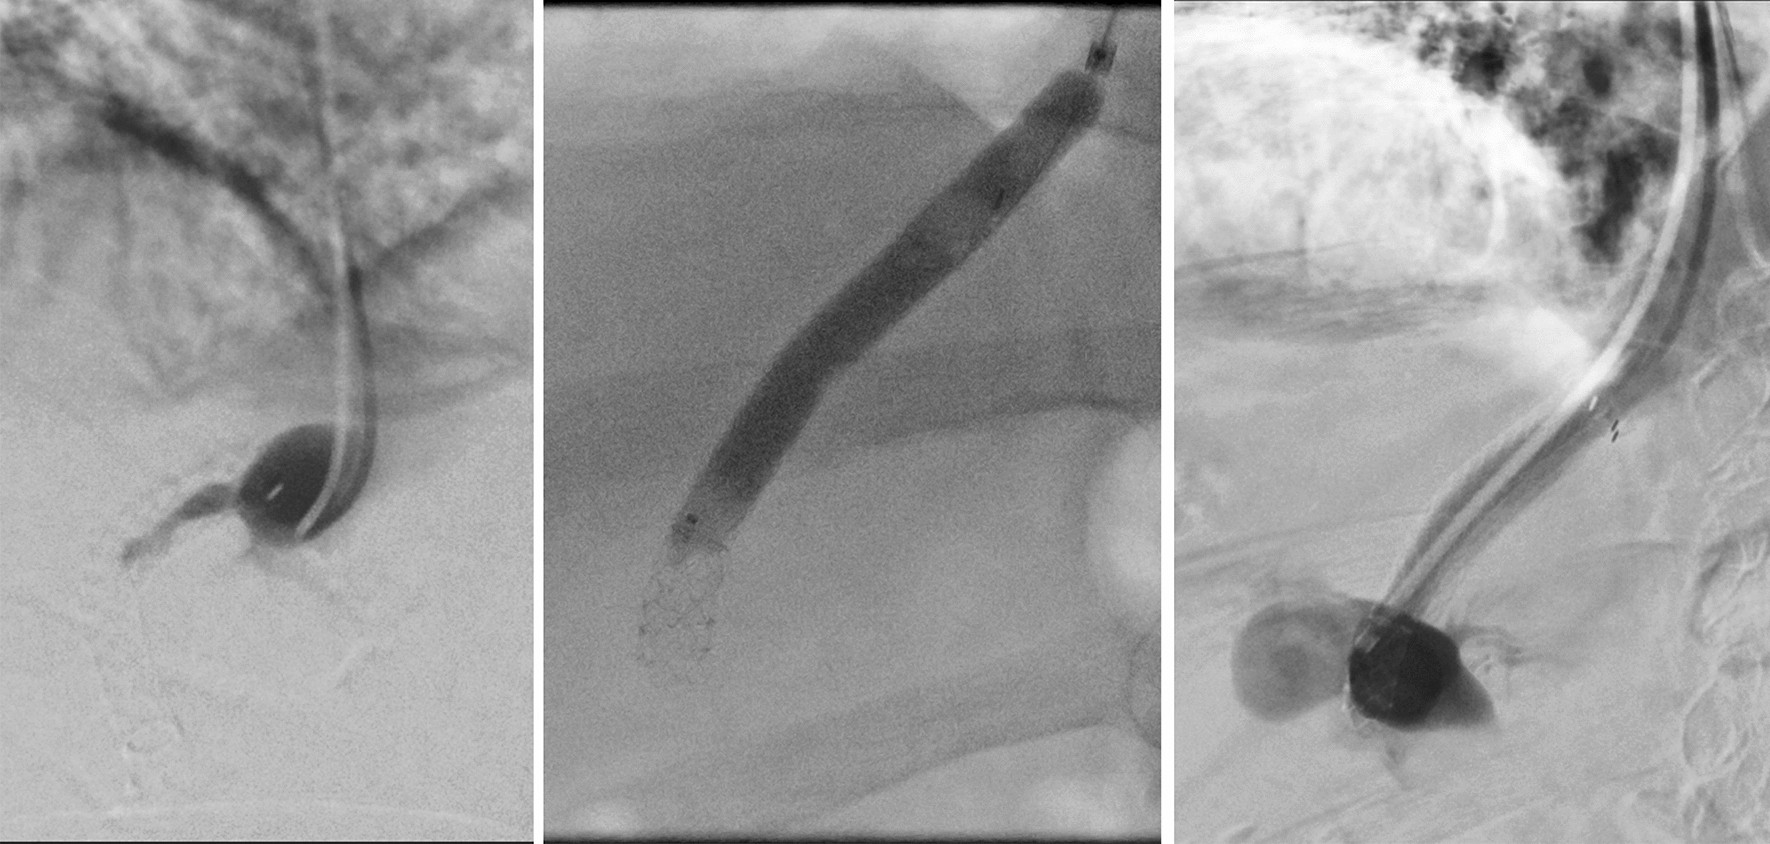

Figure 2

TIPS occlusion. Angiographic evidence of TIPS occlusion at day 23 postinterventional. The patient was previously readmitted with hydropic decompensation and sonographic evidence of early TIPS occlusion. The patency of the TIPS tract was successfully restored by balloon PTA.